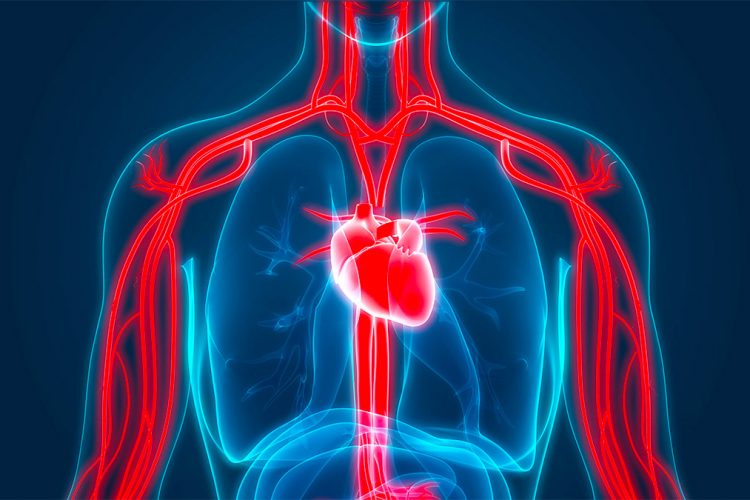

Të dyja këto sëmundje janë pjesë e sindromës metabolike, siç ndodh edhe për sëmundjet e zemrës dhe obezitetin.

Sipas të dhënave zyrtare të Fondit të Sigurimeve Shëndetësore, të cilave i referohet AgroWeb.org, tensioni i lartë i lartë i gjakut që futet tek sëmundjet kardiovaskulare bashkë me diabetin janë dy sëmundjet prej të cilave shqiptarët vuajnë më shumë.

Dëmi i shkaktuar prej saj është i gjithanshëm dhe ndikon tek veshkat dhe enët e gjakut.

Ky dëmtim nxit rritjen e tensionit të gjakut dhe rrezikut për komplikacione të tjera.

Të dyja këto sëmundje së bashku mund të rrisin rrezikun e atakut në zemër, ishemisë, dështimit të veshkave, humbjes së shikimit dhe sëmundjeve të zemrës.